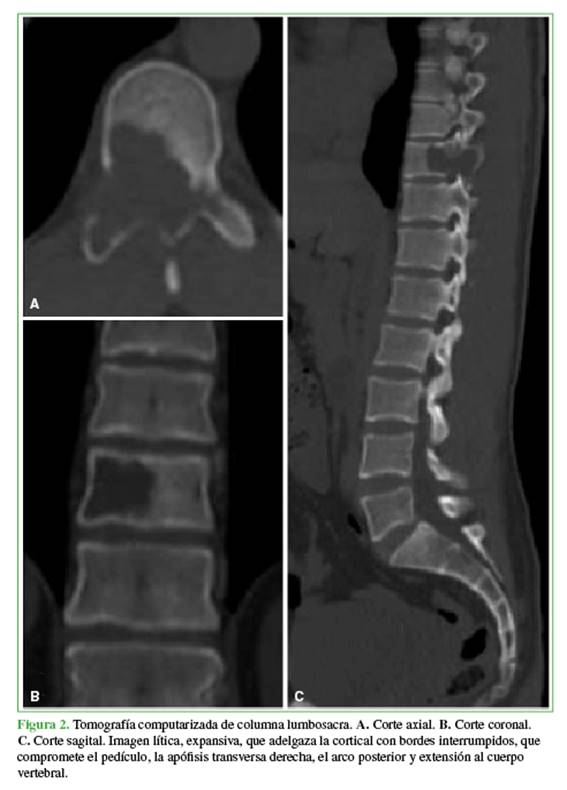

La tomografía computarizada mostró una imagen lítica expansiva, con rotura de la cortical, que comprometía el pedículo, la apófisis transversa, el arco posterior a predominio derecho y el cuerpo de T10 (<50%) (Figura 2).